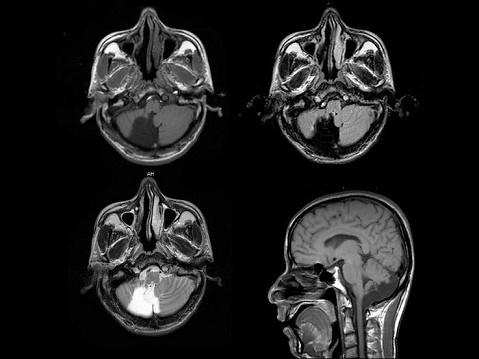

问题 男,45岁,共济失调伴癫痫发作,结合图像,最可能的诊断是?(?)

选项 A.脑干畸形 B.胼胝体发育不良 C.脑室畸形 D.Chiari畸形 E.Dandy-Walker综合征

答案 E